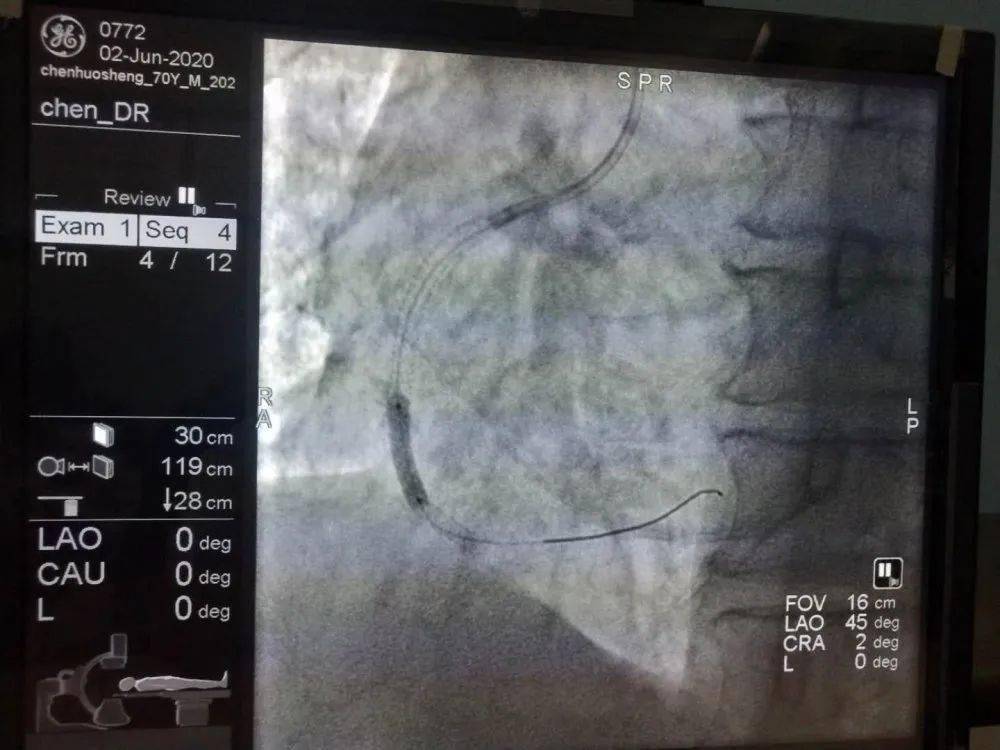

让我们了解一下造影放球囊,这是一种医疗手段,通常用于检查血管狭窄或堵塞的情况,在这个过程中,医生会将球囊插入到患者体内特定的位置,然后通过造影剂来显示血管的情况,这个过程有助于医生诊断病情,为后续的治疗提供重要的参考。